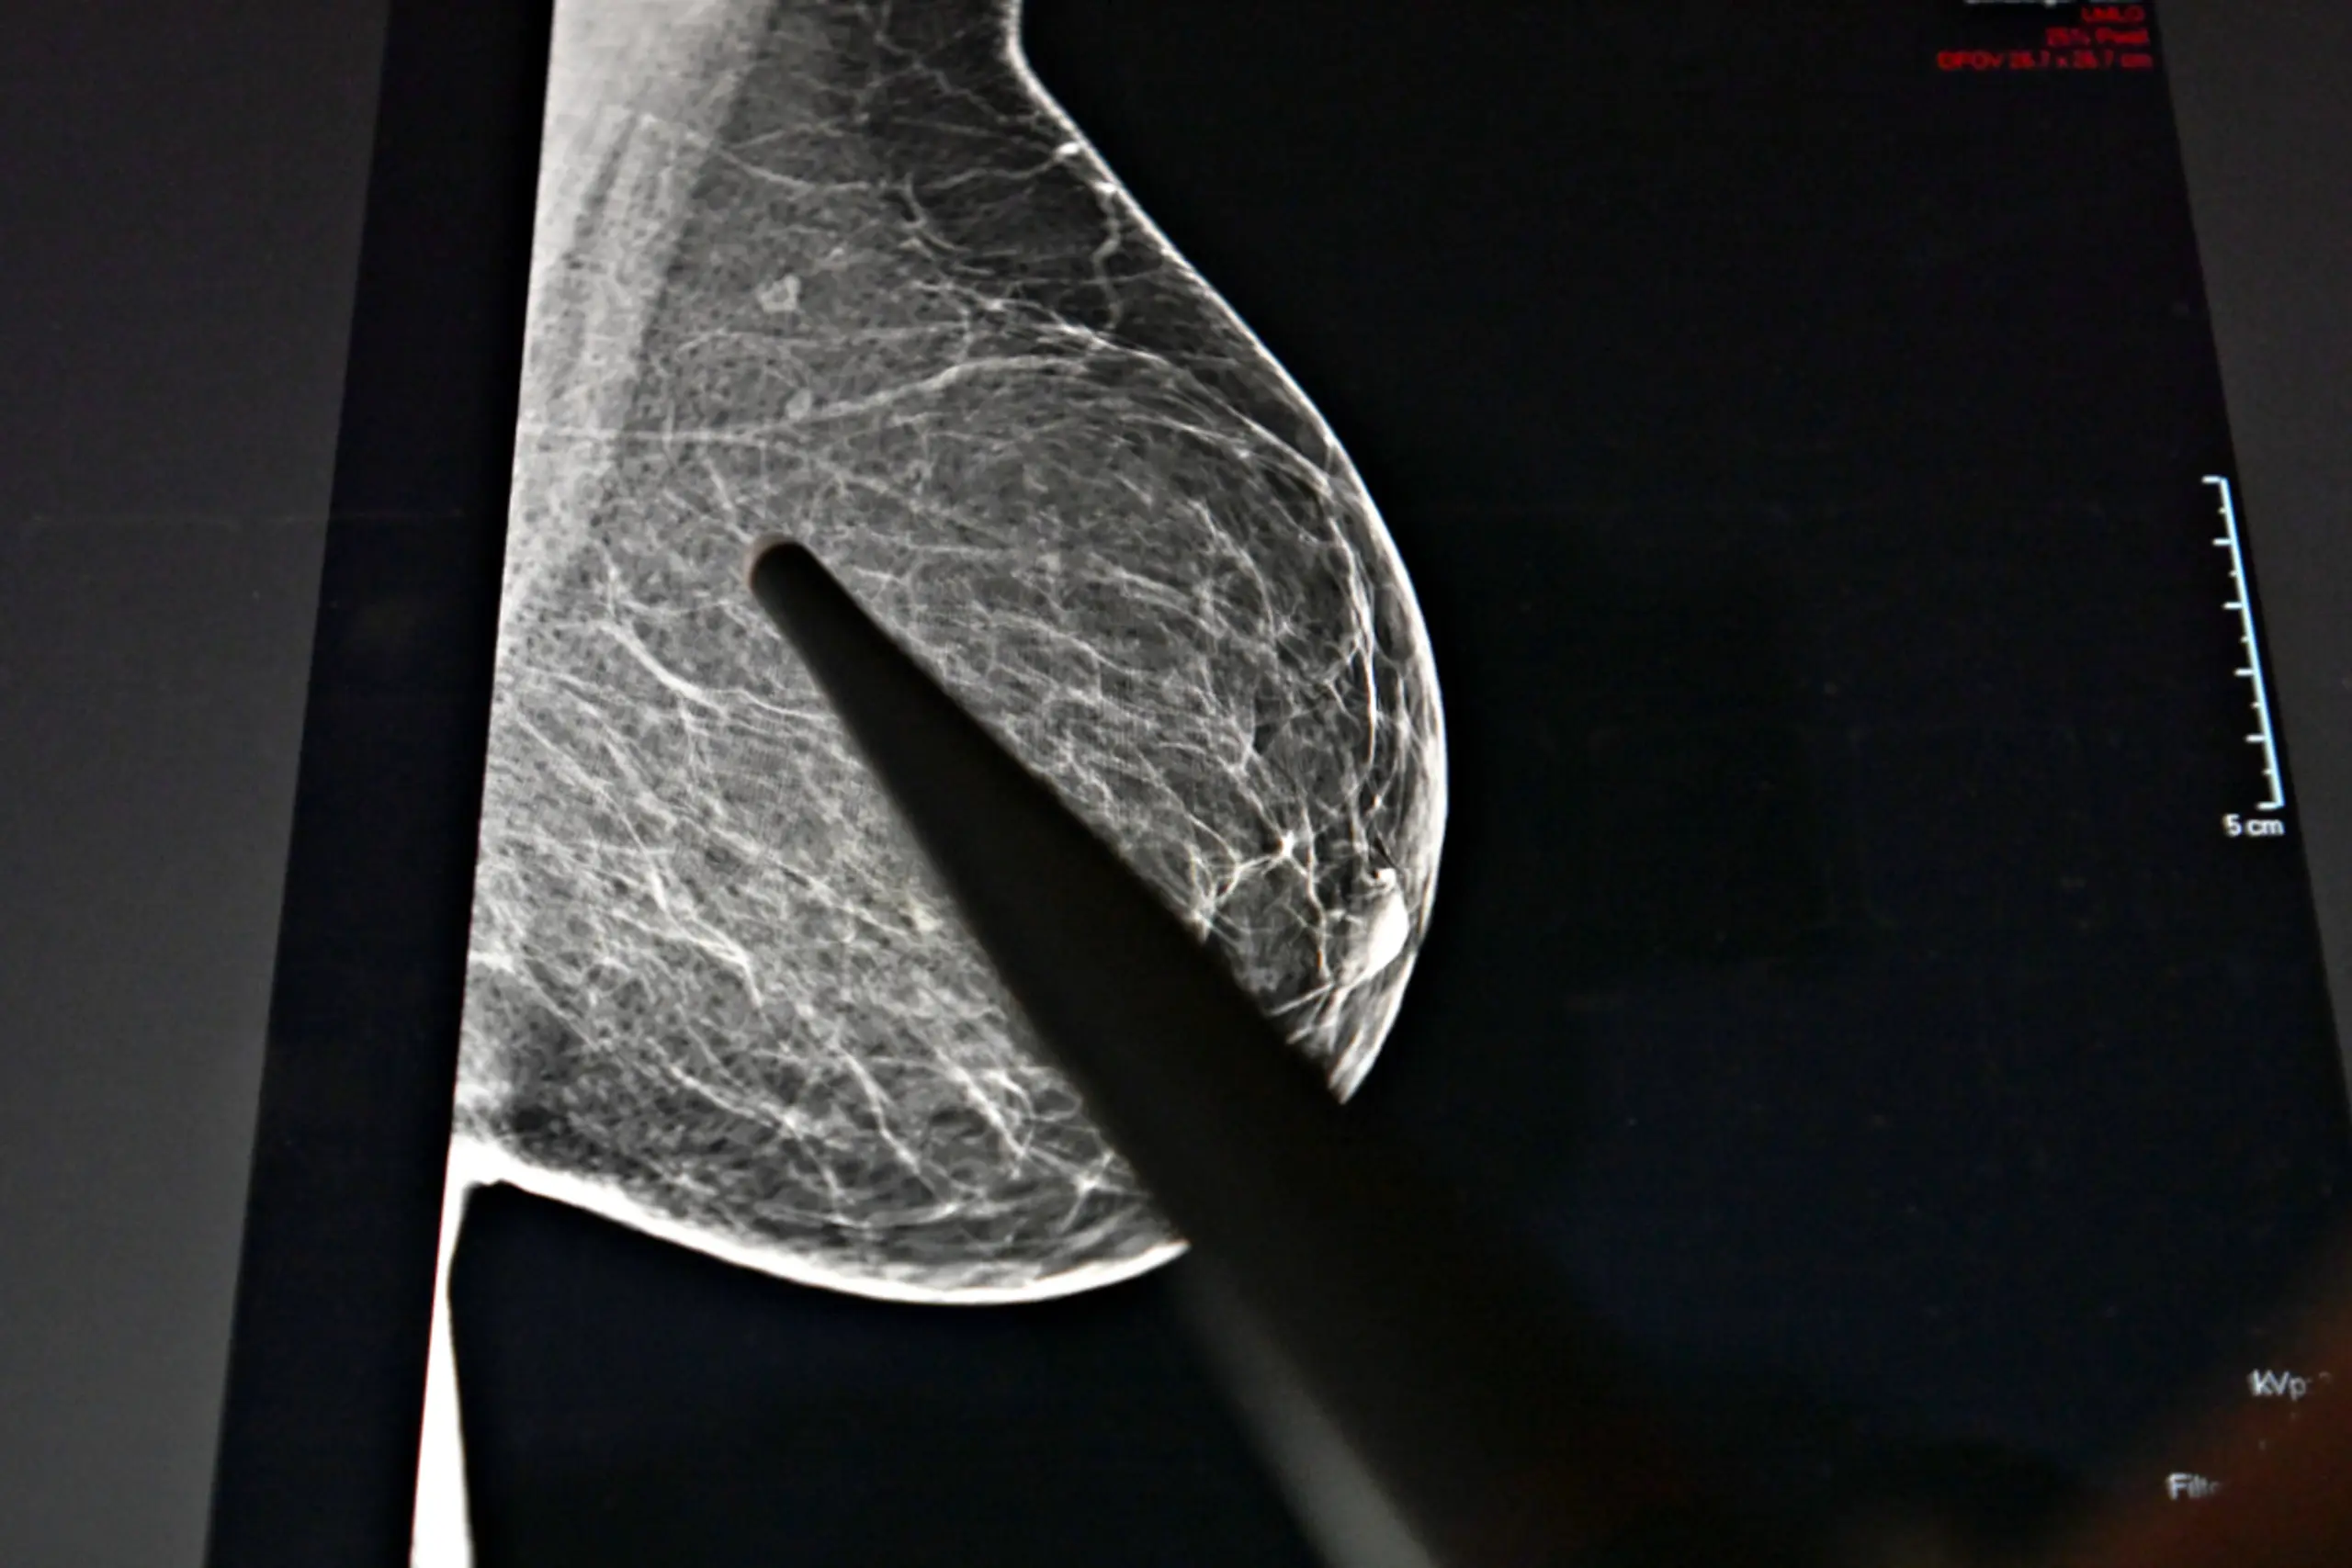

Zwischen 2014 und 2024 stieg die Zahl der jährlichen Krebsneuerkrankungen von 41.529 auf 48.360 deutlich an, während das individuelle, altersstandardisierte Erkrankungsrisiko im selben Zeitraum mit 500,8 gegenüber 497,4 je 100.000 Personen nahezu unverändert blieb. 2024 erhielten in Österreich 22.363 Frauen und 25.997 Männer eine Krebsdiagnose. Die häufigsten Diagnosen waren bösartige Tumore der Brust bei Frauen (6.959 Fälle) und bösartige Tumore der Prostata bei Männern (8.152 Fälle), gefolgt von bösartigen Tumoren der Lunge (5.533 Fälle, beide Geschlechter zusammen) und bösartigen Tumoren des Dickdarms bzw. Enddarms (4.769 Fälle, beide Geschlechter zusammen).

Bei Frauen entfielen auf Brustkrebs 2024 rund 31 Prozent der Neuerkrankungsfälle sowie 18 Prozent aller Krebssterbefälle (1.755). Bei Männern war Prostatakrebs mit knapp einem Drittel (31 Prozent) aller 2024 neu diagnostizierten bösartigen Neubildungen und einem Achtel der Sterbefälle (zwölf Prozent) die häufigste Krebsart.